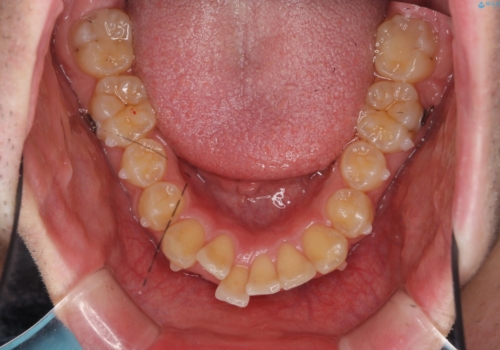

ガタつきの大きい前歯 インビザラインによるマウスピース矯正治療

- ガタつきの目立つ前歯の改善を求めて来院されました。

上顎前突、がたつきを改善すべく上顎臼歯の後方移動・ディスキングを行い歯並びの改善を計画します。

マウスピース矯正は装用時間が非常に大切です。

食事・歯ブラシ時以外の時間にしっかりとマウスピースを装着していただけたのでガタつきは大きく改善し良好な歯並びを得ることができました。